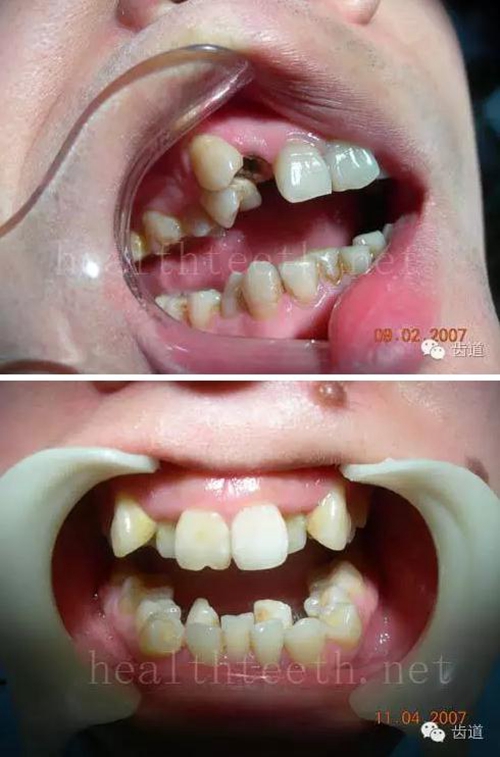

3、多生牙

病例1

47.jpg

48.jpg

49.jpg